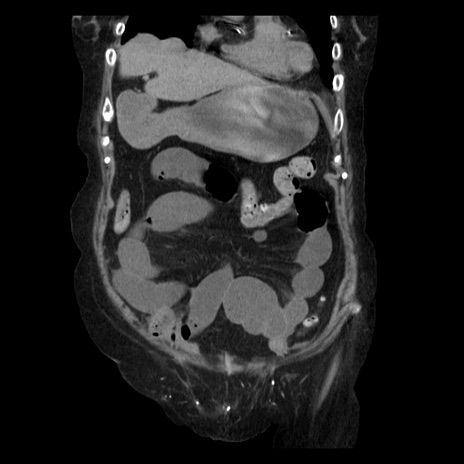

症例14(冠状断像)

【症例】 90歳代女性

【主訴】 腹痛・嘔吐

【現病歴】今朝から左側腹部痛を認めた。 経過観察していたが、嘔吐を認めたため来院。

【既往歴】 子宮癌術後

【身体所見】 意識清明、BP 127/54mmHg、P 98bpm Sp02 95%(RA)、BT 35.8°C、腹部平坦・軟腸ぜん動音聴取良好、右下腹部圧痛(+) 反跳痛なし

【データ】WBC 9800、CRP 0.46